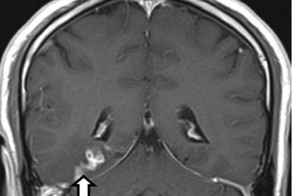

- В мозгу мужчины четыре года жил редкий червь-паразит